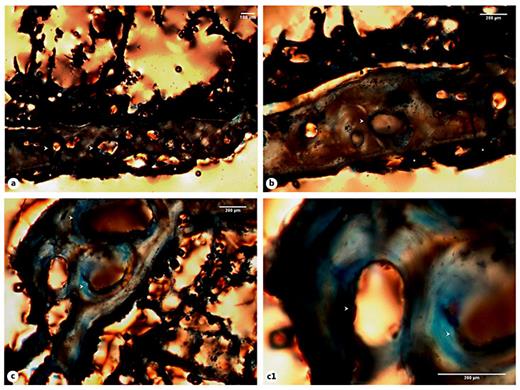

Distribution of the evidence of bone trauma in the individuals analyzed by bone element, anatomic location, and rate of consolidation

Of the 6 bone elements selected for histological analysis, 5 presented bone calluses with a consolidated and healed appearance (table 3). That is, the calluses appeared slightly elevated from the bone surface and presented a dense and smooth outer shell. Only the 4th right rib of the Sk. 1,138 individual showed an unconsolidated callus. Depending on the bone element, the callus morphology ranged from a sharp outlook to a mount-shaped or round relief (e.g. Sk. 119; fig. 1a-d). In 2 individuals (Sk. 54 and Sk. 198), the fracture had introduced slight structural changes in the bone architecture (fig. 2a-d, 3a-c). In the case of the Sk. 198 right fibula, an inefficient stabilization had caused a malalignment of the shaft with an overlap of the broken ends and subsequent bone shortening. In addition to some structural changes, a small cloaca (∼1 mm) with remodeled contours (anterior portion) and a patch of periosteal new bone formation (lateral portion) were observed in the Sk. 54 tibia bone callus. Healed fractures were seen in the ribs and at the distal extremity of the Sk. 1,196 radii, causing a slight epiphysis malalignment (fig. 4a-b2). In the unhealed rib fracture (Sk. 1,138), the broken edges presented an irregular, smooth, and polished morphology. Surrounding the affected area, deposits of periosteal new bone were seen detached from the surface. No ‘movable' joint-like structure was identified at the fractured ends (fig. 5a-d).

Evaluation of the macroscopic features of the bone callus by individual, bone element, location, and healing stage